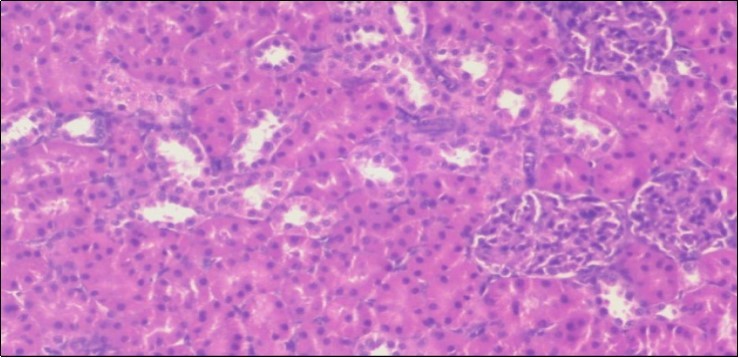

The histological examination of the kidney of the control rats fed on a standard diet showing normal rounded capsules with normal Bowman's glomeruli, round proximal tubules and elongated distal tubules with high cuboidal cells figure 1. The rats fed (HFD) showed fatty degeneration of the tubules with eosinophilic material deposition, glomerular atrophy with wide urinary space and distal tubules with extrusion of nuclei into lumen figure 2. By comparison kidneys of rats which were treated by fennel after being obese and the control rats observed partial improvement in both Bowman's capsules and proximal tubules. Note the distal tubules show less focal fatty infiltration figure 3.While examination of rats kidney that were treated by ator after obesity showed improvement in Bowman's capsules with normal glomerular and partial improvement in proximal tubules and distal tubules, figure 4. Kidney of rats that were treated by fennel and ator after obesity and the control rats showed high improvement in the tissues with normal glomerular and that Most of Bowman's capsules and renal tubules, restoring their normal appearance figure 5.

Figure 2.Photomicrogragh of kidney section of obese rat showing fatty degeneration of the tubules with eosinophilic matrial deposition, glomrerular atrophy with wide urinary space and distal tubules with extrusion of nuclei into lumen , (H&E) (40X).

Figure 3.Photomicrogragh of kidney section of treated rat with fennel herb showing partial improvement in both Bowman's capsules and proximal tubules. Note the distal tubules show less focal fatty infiltration, (H&E) (40X)

Figure 4.Photomicrogragh of kidney section of treated rat with Ator drug showing improvement in Bowman's capsules with normal glomerular and partial improvement in proximal tubules and distal tubules, (H&E) (40X).

Figure 5.Photomicrograph of kidney section of treated rat with both fennel herb and Ator drug showing highly improved tissue with normal glomerular. Note, most Bowman's capsules and renal tubules, restoring their normal appearance (star). (H&E) (40X).